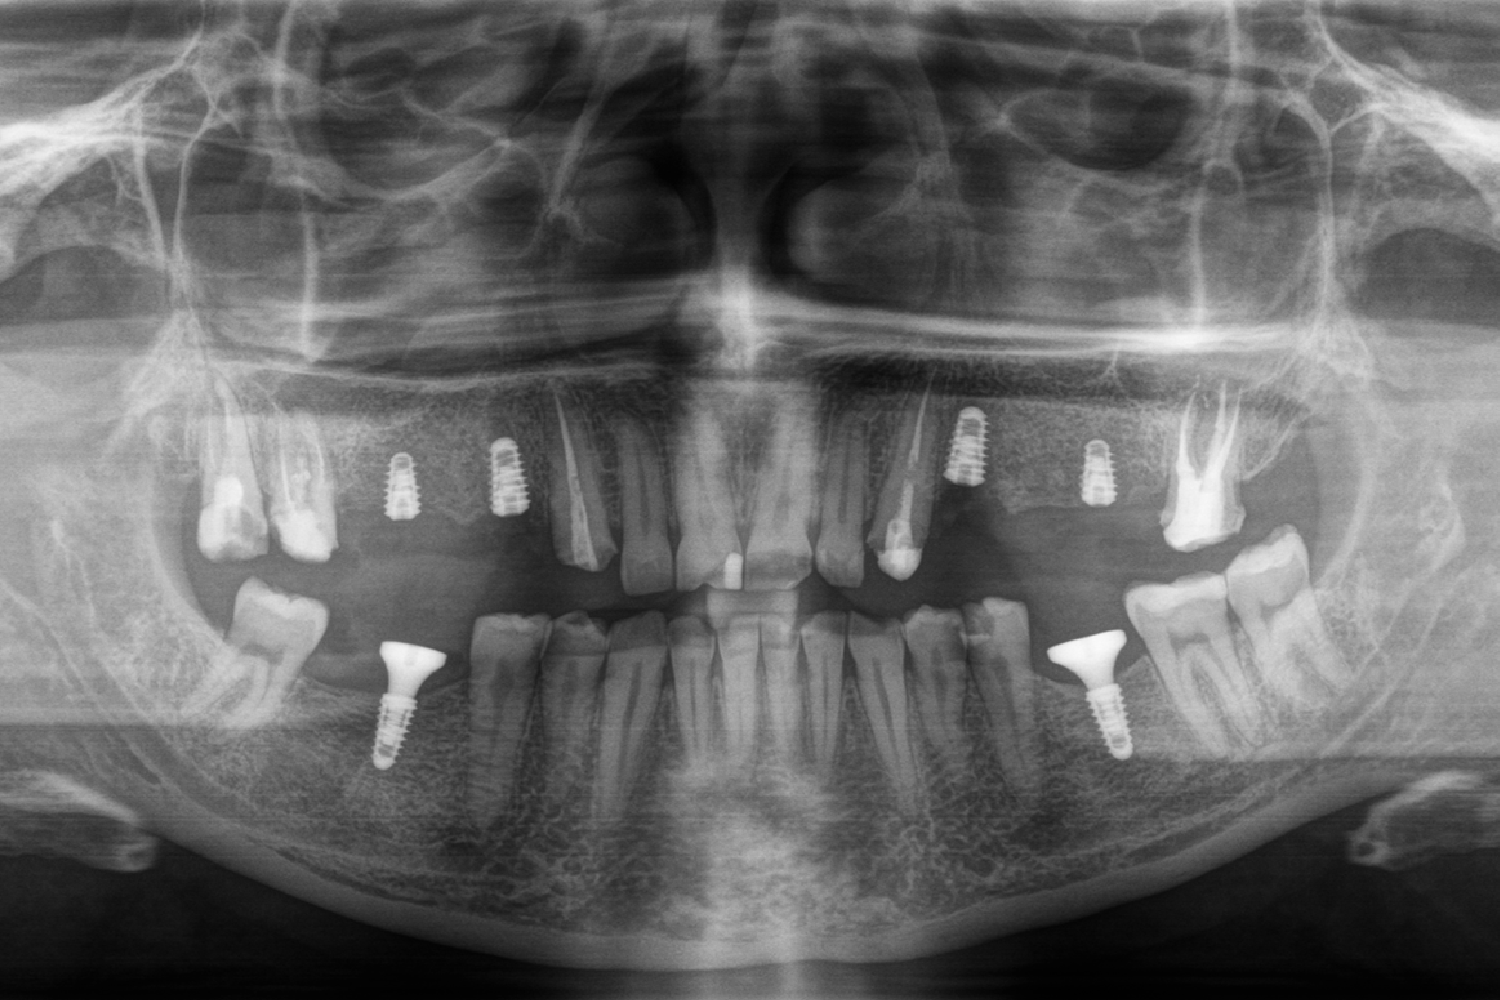

Оскільки пацієнтка не вносила корективи щодо майбутніх зубів і первинна робота лікаря повністю її задовольнила, то через 3 місяці після перенесення mock-up вона знову завітала до клініки, де для неї вже були виготовлені постійні ортопедичні конструкції. За один візит зняли mock-up модель, встановили постійні мостовидні протези та зубні коронки E-max на верхній та нижній щелепі, а також виконали художню реставрацію зубів. Цей візит тривав 3 години.